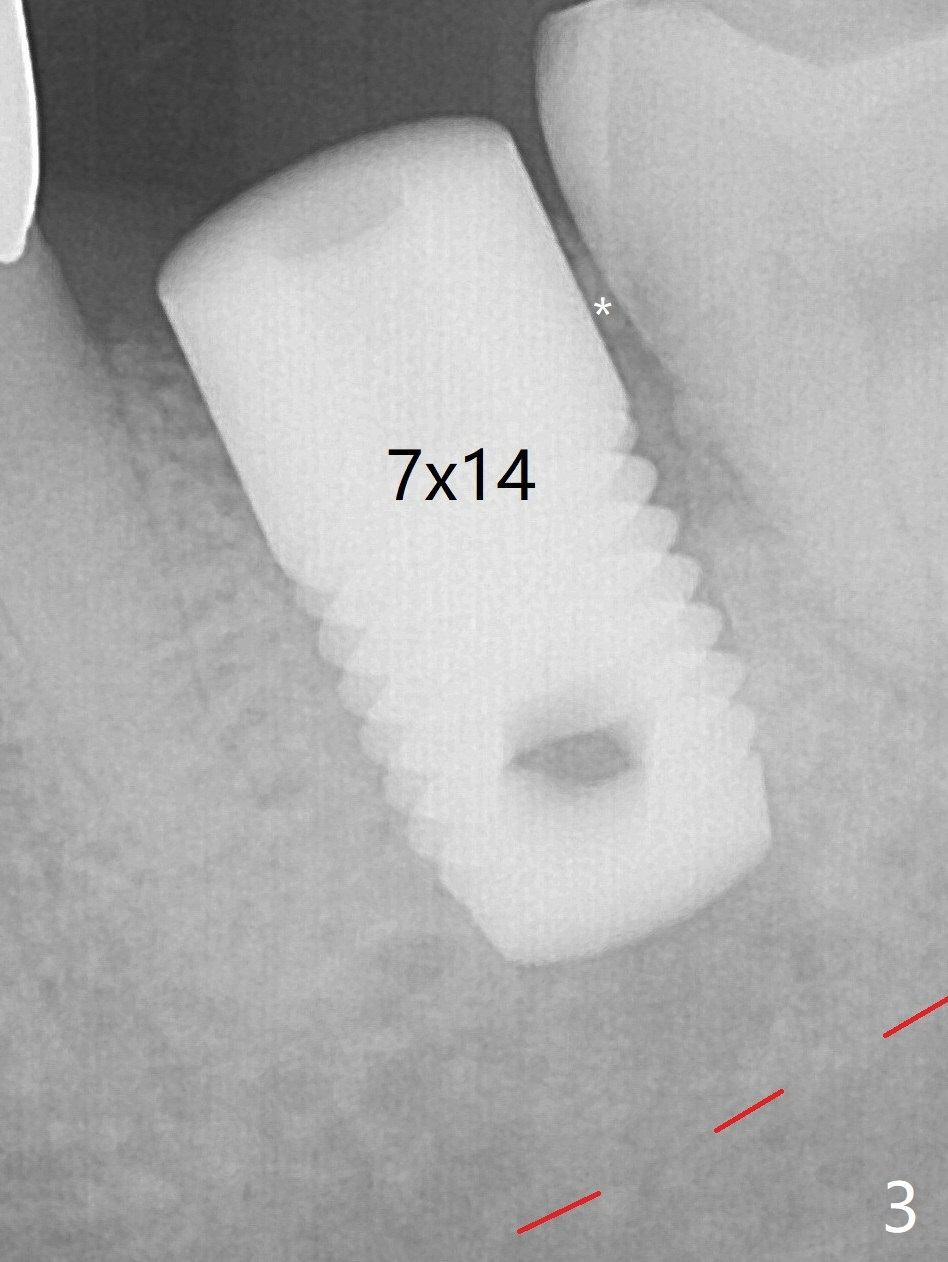

A 7x14 mm tissue-level implant is placed with ~45 Ncm (still not secure) with Vanilla graft placed mainly distolingually (Fig.3). A healing screw is placed then, followed by periodontal dressing. The red dashed line: the superior border of the Inferior Alveolar Canal. The soft and hard tissues appear to heal 3 months postop (Fig.5,6).